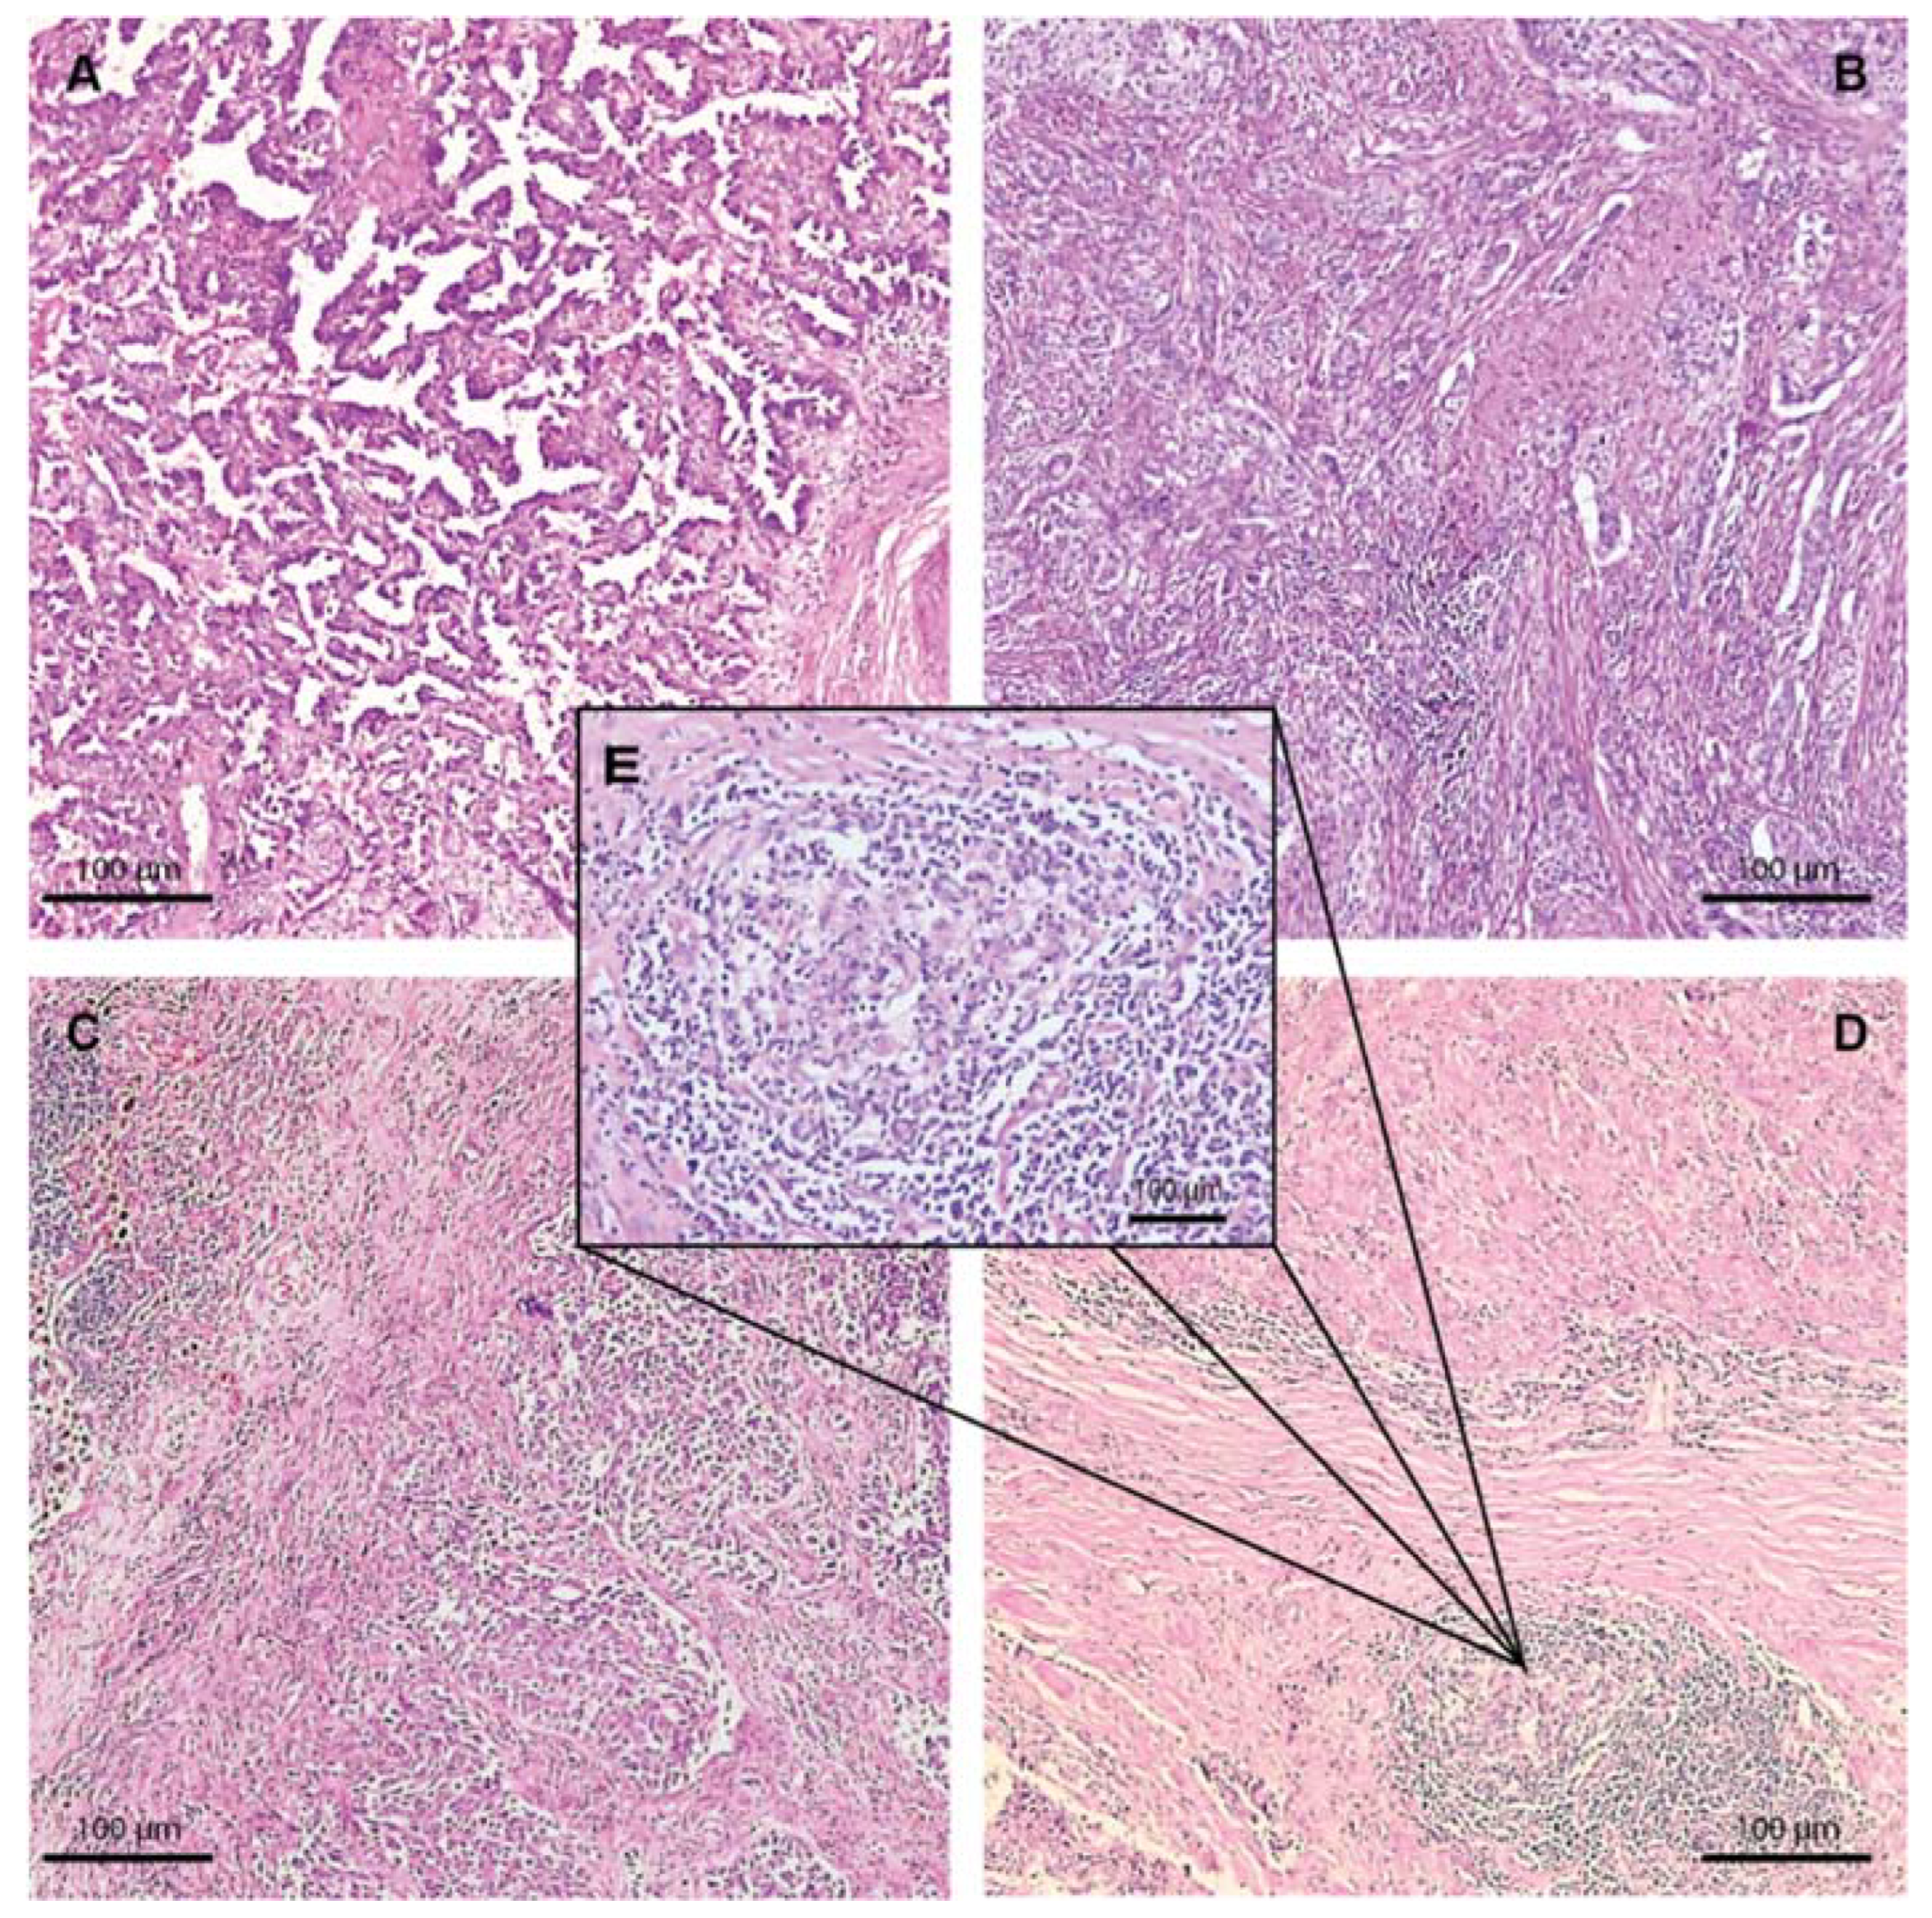

2.2. Morphologic Characteristics

4.3. Morphological Characterization